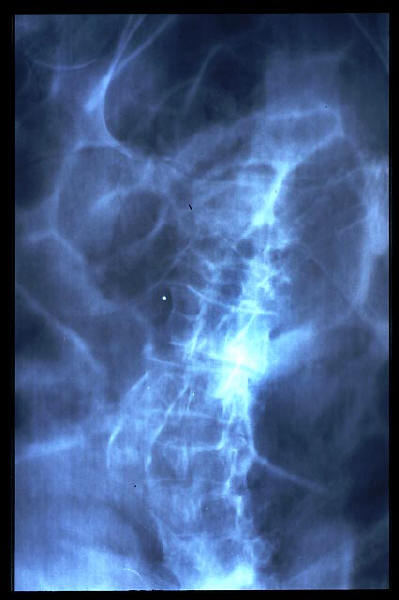

Osteoporosis. Cifosis.